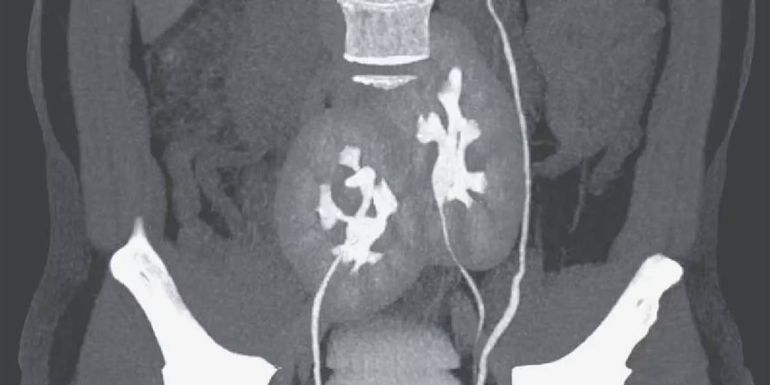

El medio científico New England Journal of Medicine dio a conocer un curioso caso médico ocurrido en San Pablo, Brasil. Se trata de un hombre de 38 años quien sufría un fuerte dolor en la zona lumbar, por lo cual decidió acudir a un hospital. Luego de un chequeo general y una tomografía, el resultado dejó impactados a los expertos. La imagen obtenida a través del estudio reveló que el paciente poseía tres riñones en lugar de dos, uno izquierdo que aparentaba ser normal y dos que se encontraban fusionados.

En el informe, los médicos comentaron que las circunstancias del paciente se tratan de una anormalidad congénita poco común. Además, aclararon que, probablemente, sea el resultado de un desarrollo embrionario en el que una estructura primitiva similar de un riñón se haya dividido en dos.